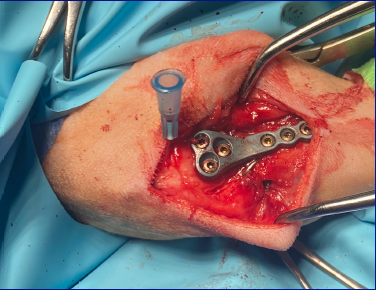

This course serves as an introduction to the management of some of the more common elbow pathologies currently encountered. It aims to guide attendees through the decision-making processes associated with elbow pain, focusing on the management of elbow dysplasia and humeral intercondylar fissure during the morning session.

In the afternoon, there will be a wet lab where attendees can practice screw placement. This session will also cover both medial and lateral approaches to the humeral condyle, as well as the placement of implants to effectively treat these fractures. This course includes both a wet and dry lab.